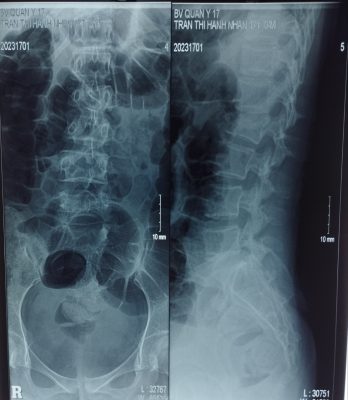

– Kết quả chụp phim chẩn đoán: chấn thương mất vững cột sống vỡ lún L2, có tổn thương thành sau thân đốt sống.

Phim Xquang cột sống